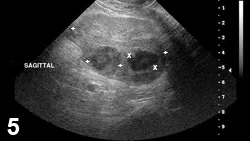

A sagittal ultrasound image shows two distinct structures within a veterinary patient's abdomen, marked with crosses for measurement. The image highlights the surrounding tissue and provides a clear view of the anatomical features being assessed.

FIGURE 5

Prostatic adenocarcinoma. Sagittal image of an intact canine prostate showing characteristic BPH striations ventrally, but hypoechoic nodules (cursors) present within the dorsal parenchyma. Nonhomogenous prostatic parenchymal appearance should prompt evaluation with a biopsy.

• Multiple prostatic pathologies can be present in any patient (Figure 5).